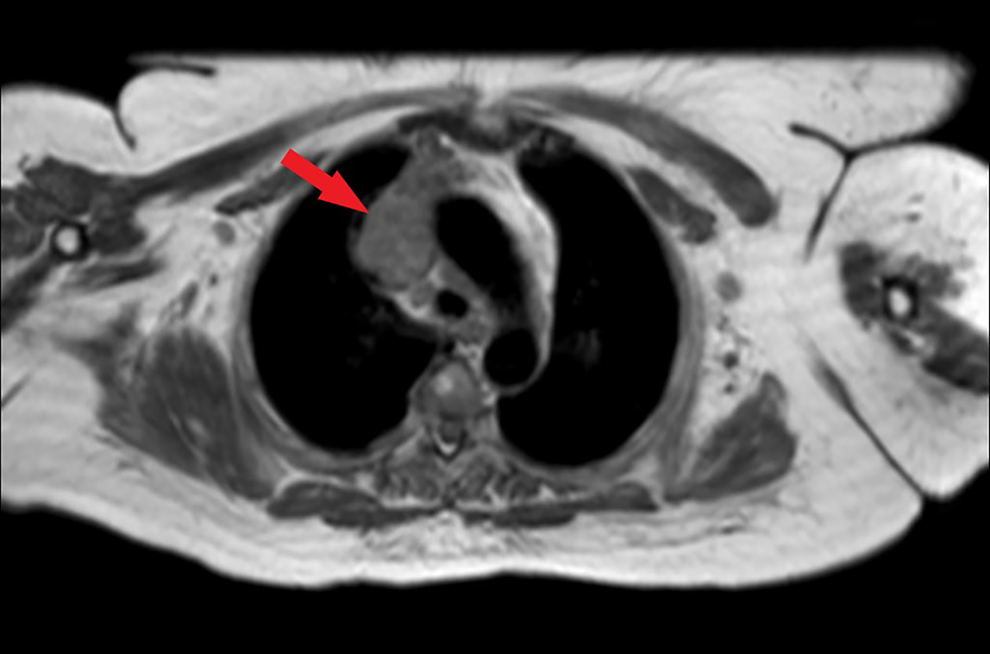

A chest radiograph is performed and shows an enlarged mediastinum suggestive of a mediastinal mass (Figure 1). Based on these findings, a magnetic resonance imaging scan of the chest is performed, which confirms an anterior mediastinal mass (Figure 2). The mass is well-defined without invasion of surrounding structures and does not show areas of hemorrhage, necrosis, calcification, or cystic change.

T1-weighted magnetic resonance imaging confirms the presence of an anterior mediastinal mass (arrow).